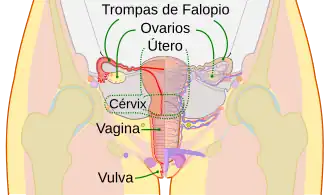

En anatomía, las trompas uterinas,[1] también conocidas como tubas uterinas, trompas de Falopio,[2] salpinges uterinas u oviductos, son dos conductos musculares separados, que conectan los ovarios y el útero o matriz de los mamíferos.

Existen dos oviductos, cada uno conecta un ovario con el sector superior y lateral del útero.

Se extienden a lo largo del margen superior de los ligamentos anchos del útero, desde su extremo medial o "cuernos del útero" hasta su extremo lateral en la superficie del ovario.

Cada trompa se ancla en su cara inferior, mediante una doble hoja de peritoneo llamada mesosálpinx y se abre a la cavidad peritoneal.[7][8][5][3]